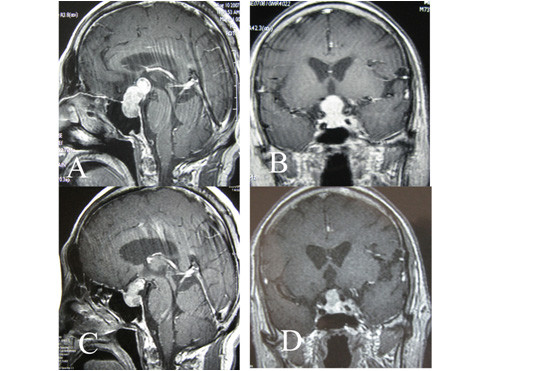

老年颅内良性肿瘤:当患者不能耐受开颅手术时,肿瘤对放射外科治疗相对敏感时,射波刀低分割治疗颅内良性肿瘤有明显优势。将治疗肿瘤的剂量分割成3-5次,可以提高控制肿瘤的剂量,同时减轻副反应。如图6,患者74岁,右侧海绵窦海绵状血管瘤,肿瘤大,不能耐受开颅手术,实施周边剂量21Gy,分割成3次照射,治疗后3个月肿瘤缩小,患者的头痛症状减轻,治疗后14个月,肿瘤进一步缩小。图7为75岁的垂体瘤患者,肿瘤较大,但是患者有内科疾病不能耐受手术,实施周边剂量22.5Gy,分割3次治疗。尽管肿瘤紧贴视神经视交叉,射波刀治疗后,患者视力未受影响,治疗后8个月复查MRI显示肿瘤缩小。

图6:右侧海绵窦海绵状血管瘤(影像学诊断)射波刀治疗前后的比较。A: 射波刀治疗前MRI;B:射波刀治疗后3个月,复查MRI显示肿瘤明显缩小。C和D:治疗后14个月,肿瘤进一步缩小,患者无不适。

图7:高龄垂体瘤患者射波刀治疗前后增强MRI比较。A和B: 射波刀治疗前;C和D:射波刀治疗后8个月,肿瘤缩小,患者视力未受影响。